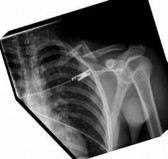

Figure 3a Figure 3b Figure 3c Figure 3a is the initial radiograph of a 19-year-old man who sustained a closed clavicle fracture. Figures 3b and 3c show postoperative radiographs. If the patient had been treated nonsurgically, which of the following would most likely occur?